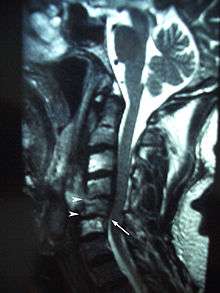

MRI showing osteoradionecrosis in the cervical vertebrae following radiotherapy for laryngeal cancer.

Osteoradionecrosis is a possible complication following radiotherapy where an area of bone does not heal from irradiation. Irradiation of bones causes damage to osteocytes and impairs the blood supply. The affected hard tissues become hypovascular (reduced number of blood vessels), hypocellular (reduced number of cells) and hypoxic (low levels of oxygen). Osteoradionecrosis usually occurs in the mandible, and causes chronic pain and surface ulceration. Prevention of osteradionecrosis is part of the reason all teeth of questionable prognosis are removed before the start of a course of radiotherapy.[1]